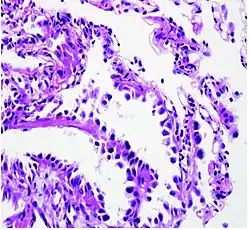

.jpg)

The majority of lung cancers can be characterized as either small cell lung cancer (SCLC) or non-small cell lung cancer (NSCLC). Lung adenocarcinoma is one of the three major subtypes of NSCLC, which also include squamous carcinoma and large cell carcinoma.[15]

Adenocarcinoma of the lung tends to stain mucin positive as it is derived from the mucus-producing glands of the lungs. Similar to other adenocarcinoma, if this tumor is well differentiated (low grade) it will resemble the normal glandular structure. Poorly differentiated adenocarcinoma will not resemble the normal glands (high grade) and will be detected by seeing that they stain positive for mucin (which the glands produce). Adenocarcinoma can also be distinguished by staining for TTF-1, a cell marker for adenocarcinoma.[29]

As discussed previously, the category of adenocarcinoma includes are range of subtypes, and any one tumor tends to be heterogeneous in composition. Several major subtypes are currently recognized by the World Health Organization (WHO)[1] and the International Association for the Study of Lung Cancer (IASLC) / American Thoracic Society (ATS) / European Respiratory Society (ERS):[30][31][32] lepidic predominant adenocarcinoma, acinar predominant adenocarcinoma, papillary predominant adenocarcinoma, micropapillary predominant adenocarcinoma, solid predominant adenocarcinoma, and solid predominant with mucin production. In as many as 80% of these tumors, components of more than one subtype will be recognized. Surgically resected tumors should be classified by comprehensive histological subtyping, describing patterns of involvement in increments of 5%. The predominant histologic subtype is then used to classify the tumor overall.[2] The predominant subtype is prognostic for survival after complete resection.[33]

To reveal the adenocarcinomatous lineage of the solid variant, demonstration of intracellular mucin production may be performed. Foci of squamous metaplasia and dysplasia may be present in the epithelium proximal to adenocarcinomas, but these are not the precursor lesions for this tumor. Rather, the precursor of peripheral adenocarcinomas has been termed atypical adenomatous hyperplasia (AAH).[10] Microscopically, AAH is a well-demarcated focus of epithelial proliferation, containing cuboidal to low-columnar cells resembling club cells or type II pneumocytes.[10] These demonstrate various degrees of cytologic atypia, including hyperchromasia, pleomorphism, prominent nucleoli.[10] However, the atypia is not to the extent as seen in frank adenocarcinomas.[10] Lesions of AAH are monoclonal, and they share many of the molecular aberrations (like KRAS mutations) that are associated with adenocarcinomas.[10]